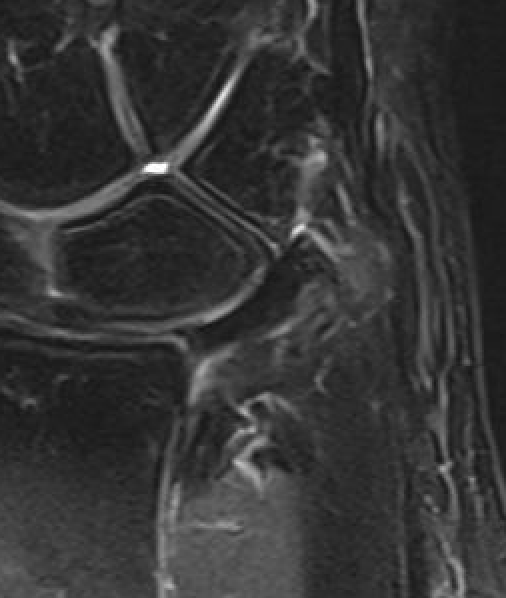

TFCC tears

Ulna sided tear

Radial sided TFCC tear

Central TFCC tear

Ulno-carpal abutment

Ulnocarpal abutment and lunate chondromalacia